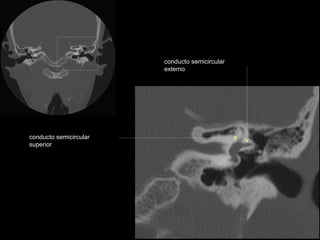

conducto semicircular externo

conducto semicircular

superior

conducto semicircular superior